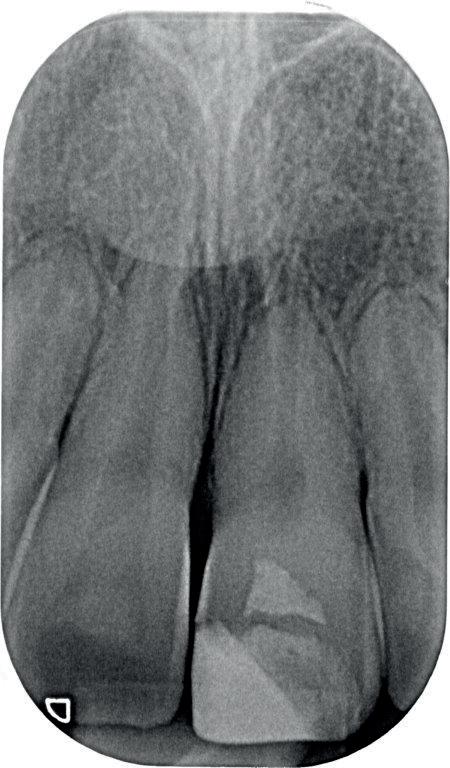

Voordat je aan een wortelkanaalbehandeling begint, zorg je voor (of maak je) een goede beginfoto waar het te behandelen gebitselement volledig op staat afgebeeld. Deze foto geeft essentiële informatie: de grootte van de pulpakamer en de ligging ervan; het aantal en de vorm van de wortels en de breedte van hun wortelkanalen en de lengte van de wortels. Hiermee kan je de DETI-score bepalen en de moeilijkheidsgraad inschatten. De grootte en de ligging van de pulpakamer op de röntgenfoto in combinatie met de ideale anatomische vorm, zoals in foto 1 is aangegeven, bepaalt de uiteindelijke vormgeving van de opening. Bij de molaren liggen de kanaalingangen in de buurt van de knobbeltoppen. Als die niet meer in originele staat

1. De locatie van de kanaalingangen ten opzichte van de occlusale morfologie (rood). In zwart is de ideale of standaard opening ingetekend. De uiteindelijke vorm van de opening is voorts ook afhankelijk van de klinische situatie, die vooral vanuit een goede begin foto wordt verkregen.